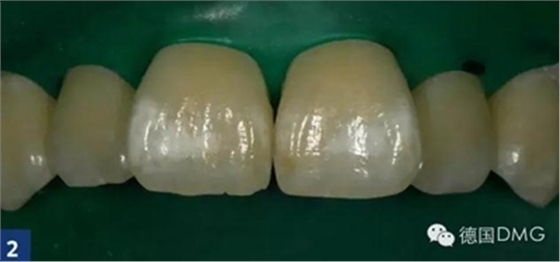

首先, 應(yīng)清潔牙齒或者由您的私人牙醫(yī)為您處理.應(yīng)用橡皮障之后 (Fig. 2),